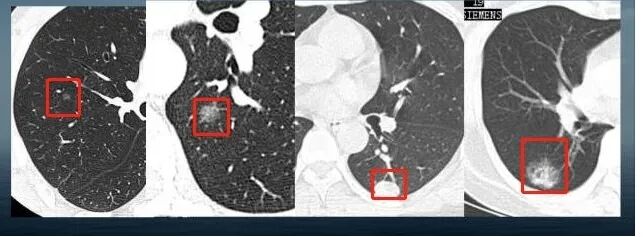

我究竟长什么样呢?在胸部CT上,我主要表现为:直径≤3cm,局灶性、类圆形,密度增高的实性或亚实性的肺部阴影